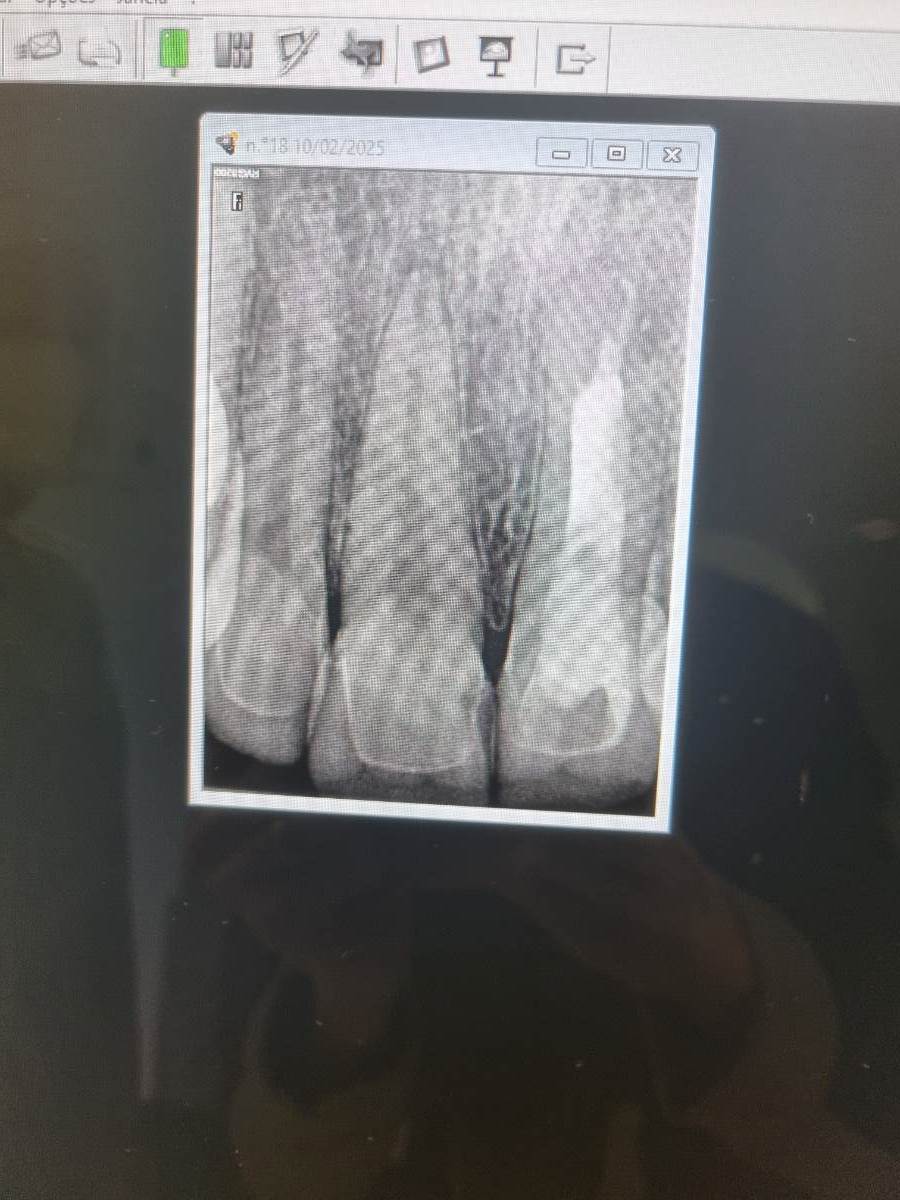

Елена2721 Опубликовано 10 февраля, 2025 Поделиться Опубликовано 10 февраля, 2025 Доброго времени суток! Мне в начале января установили виниры на 4 верхних резца. Установка происходила без анестезии, боль была адская, ещё неделю после установки половина челюсти горела. Стоматолог на приёме сказала что это нормально. Прошёл месяц, но осталась пульсирующая боль в области корня правого верхнего зуба. Сам зуб очень чувствительный и начал пошатываться. Заставила врача сделать рентген, она признала что есть воспаление, но отрицает свою ответственность, не знает откуда воспаление и тд. Прописла пить ибупрофен. Но доверия врач больше не вызывает. Подскажите пожалуйста, судя по снимку, насколько все плохо и как можно спасти сам зуб и нерв? Ссылка на комментарий

red_butler Опубликовано 11 февраля, 2025 Поделиться Опубликовано 11 февраля, 2025 Здравствуйте, судя по снимку и Вашим словам, требуется лечение корневого канала. Ссылка на комментарий